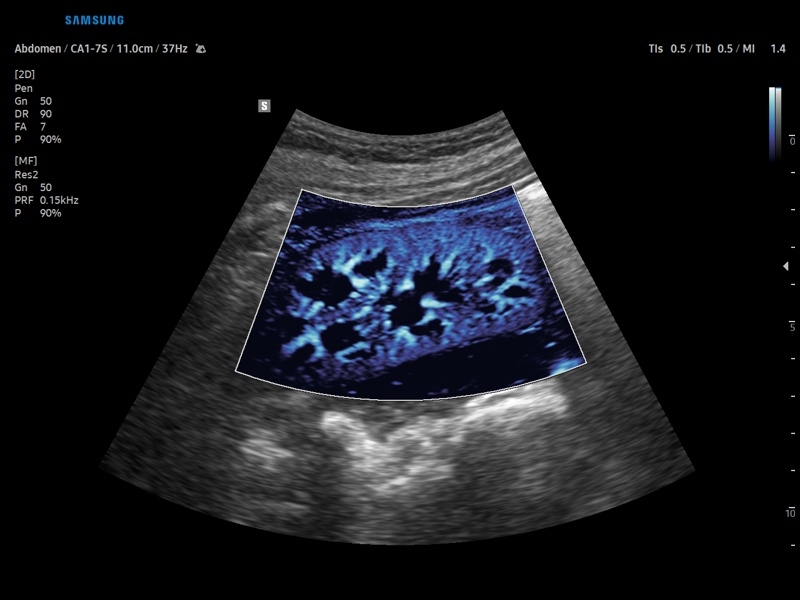

• Модуль CEUS+ (Contrast Enchansment UltraSound) - программа, позволяющая проводить обследование с применением контрастных агентов.

• Модуль MV-Flow – программа (режим), позволяющая визуализировать кровоток в микроциркуляторном русле с высоким разрешением без использования контраста.